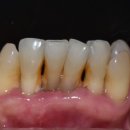

안녕하세요, 더바름치과입니다! 매년 (6월쯤)이맘때쯤이면 잠실 치과, 더바름은 임시치아대회로... 임시치아는 기공소에서 제작되어 오긴 하지만 형태를 잘 알고 다듬을줄 알아야 하거든요. 각자의 실력을 한...

바른진료 ✅ 더바름치과병원✅(20250724)

많은 경험과 노하우 그리고 오랜기간 손발을 맞춰온 앞니 전문 기공소까지 저희 잠실치과, 더바름 에서 앞니 상담 받아보세요~ 잠실치과, 더바름 에서는 환자분의 통증을 줄여드리기위한 컴퓨터 무통 마취 기계...

치과, 더 바름(20150929)

저희 더바름치과는 앞니 재치료도 많이 하고 있습니다. 이런 부분은 심미성까지 부여하기 위해 앞니만 따로 보철을 만드는 2015년 개원 이후 쭉~ 앞니 전문 기공소와 협력하고 있습니다. 이분은 사실... 다른 곳도...